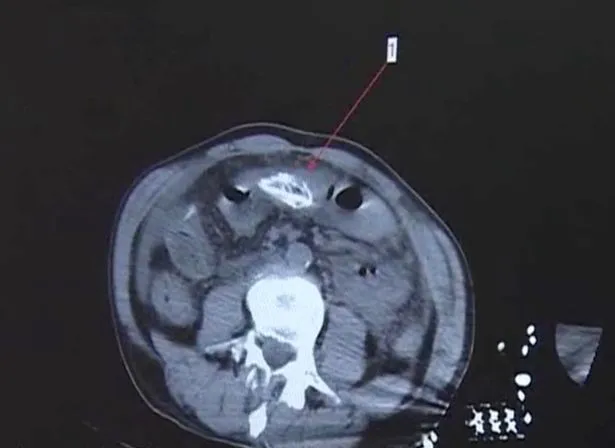

อย่างไรก็ตาม ทีมแพทย์ได้ทำการ CT Scan เพื่อหาสาเหตุของความเจ็บป่วยของชายอายุ 50 ปี เนื่องจากเมื่อมาถึงโรงพยาบาลเขามีภาวะติดเชื้อรุนแรง จนนำไปสู่ภาวะช็อก และไม่สามารถสื่อสารกับแพทย์ได้ และในระหว่างการ CT Scan แพทย์ได้ตั้งข้อสงสัยว่า อาจมีสิ่งแปลกปลอมอยู่ในช่องท้องของผู้ป่วยรายนี้ แต่ก็ไม่สามารถบอกได้ว่ามันคืออะไร

ด้วยเหตุนี้ทีมแพทย์จึงทำการส่องกล้องเพื่อตรวจลำไส้ใหญ่ของผู้ป่วย และพบว่ามีปลาไหลในเอเชียอยู่ในสู่ช่องท้องของผู้ป่วย แพทย์จึงทำการผ่าตัดฉุกเฉินเพื่อนำปลาไหลออกจากลำไส้ โดยแพทย์เปิดหน้าท้องของเขา และพบว่าเต็มไปด้วยของเสียจำนวนมาก รวมทั้งอุจจาระและหนอง ที่เกิดจากการติดเชื้ออย่างรุนแรง

จากคลิปวิดีโอที่น่ากลัวนี้แสดงให้เห็นว่า แพทย์ได้ผ่าตัดนำปลาไหลขนาด 15 นิ้ว ออกมาจากช่องท้องของผู้ป่วยในสภาพที่ตายไปแล้ว และมันทำให้เกิดการปนเปื้อนของแบคทีเรียอย่างรุนแรงในช่องท้อง อุจจาระมีการรั่วไหลเข้าสู่ร่างกายของผู้ป่วย เนื่องจากการแตกในลำไส้ใหญ่ sigmoid หรือที่เรียกว่าลำไส้ใหญ่เชิงกราน ซึ่งเป็นส่วนของลำไส้ใหญ่ใกล้กับทวารหนัก